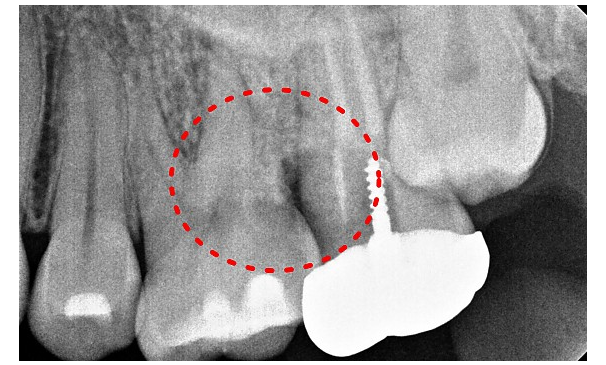

유OO님 전후사진 | 치료 기간 : 4주

치료 전

치료 후